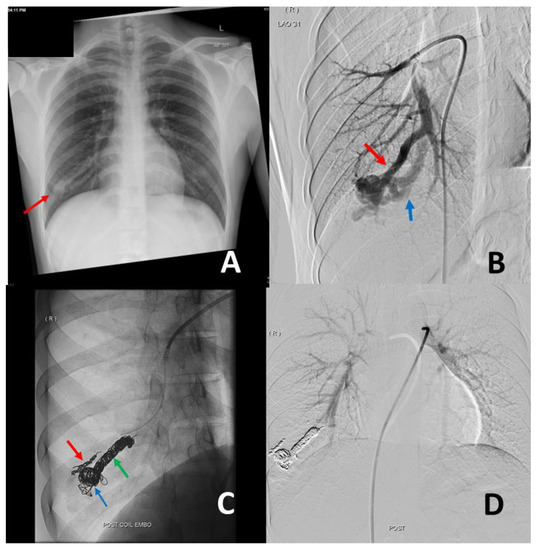

- (1)

3. Management of PAVM